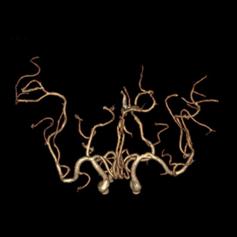

病例24:双侧大脑中动脉M1段动脉瘤合并基底动脉开窗畸形